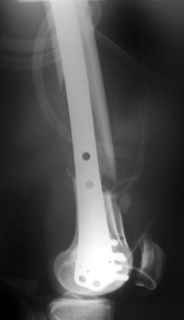

This is what we have done... As generally true for LISS look at the bone not the hardware.

There are two more srews above. The one not completely in got damaged head.

Zsolt